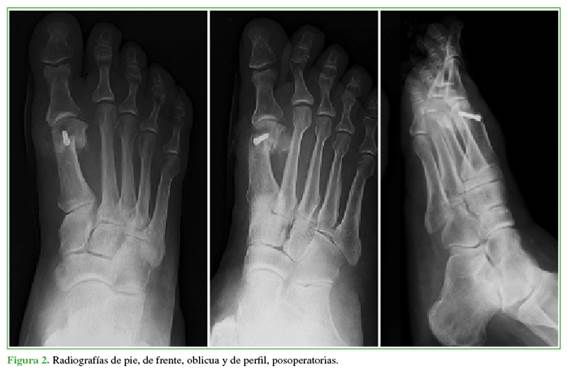

A todos los pacientes se les tomaron radiografías anteroposterior, latero-lateral con apoyo y oblicua de pie antes de la cirugía (Figura 1), en el posoperatorio (Figura 2) y a los 18 meses de la intervención (Figura 3) para establecer el ángulo intermetatarsiano (IM), el ángulo del hallux valgus (HV), el ángulo articular metatarsiano distal (AMD), la congruencia de la articulación metatarsofalángica, el ángulo interfalángico, la altura del M1, el grado de deformidad, el grado de lesión, la movilidad articular del hallux, la presencia de dolor, y para planificar la cirugía.

Se tomaron radiografías del pie de frente, oblicua y de perfil en el posoperatorio inmediato para evaluar una posible pérdida de la reducción. Se consideró un resultado radiográfico definitivo a los 18 meses o más de la cirugía.